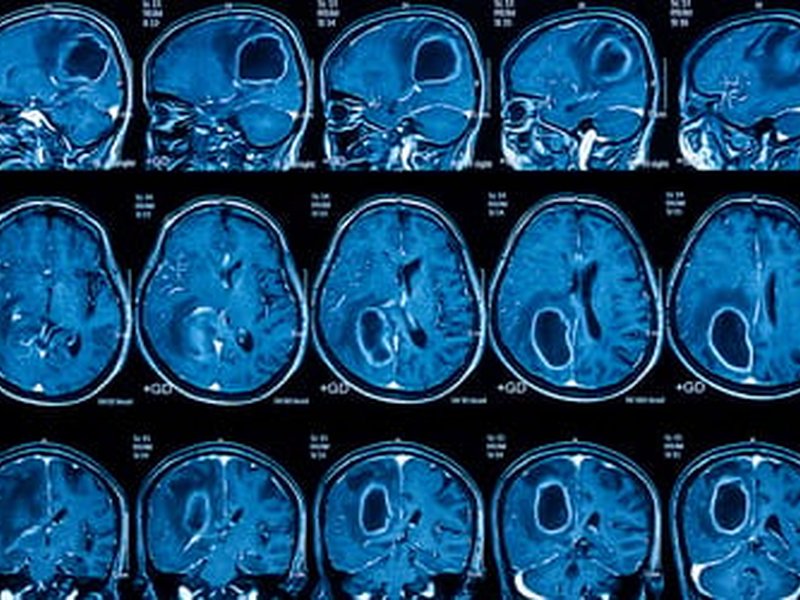

Agydaganat ellen orrcsepp?

Bár az orrcseppekről elsősorban a nátha kezelése jut az ember eszébe, amerikai szakemberek valami egészen rendkívüli alkalmazásáról számoltak be: a legagresszívebb agydaganat kezelésére is bevethető egy speciális orrcsepp, kiváltva a szike szükségességét. Az állatkísérletek ígéretesek, azonban a humán alkalmazás bevezetése előtt egyelőre számos kihívás áll.